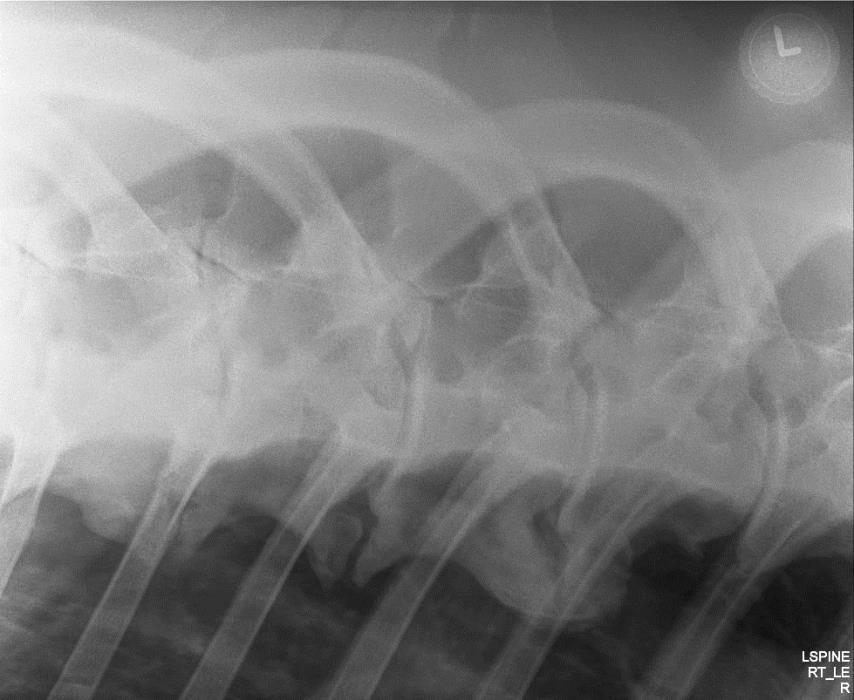

The development and advancement of digital radiography has allowed for diagnostic field radiographs of the neck and some parts of the thoracolumbar spine. Lateral images of the cervical spine may demonstrate the presence of osteoarthritis, vertebral anomalies, and abnormalities of the vertebral canal, such as stenosis. One can also acquire very diagnostic oblique images of the cervical articular processes with practice (Figures 2A and 2B).

Portable generators in the 80 to 90 kVp range enable one to acquire diagnostic images of some thoracic vertebral bodies and articular process joints in the field. Care needs to be taken to minimize radiation exposure for the operators.

RFigure 2A: Field radiograph using portable machine and DR technology demonstrating enlargement of an articular process joint. Cranial is to the left.

Fig. 2A: Field radiograph using portable machine and DR technology demonstrating enlargement of an articular process joint. Cranial is to the left.

Fig. 3 Oblique thoracic image of a 16.2 hand Warmblood, 84 KVP/.18 sec generator, demonstrating marked, multifocal, ventral spondylosis. Such lesions associated with stiffness and poor performance, in the author’s experience

Image courtesy of Dr. Richard D. Mitchell.

Figure 3: Oblique thoracic image of a 16.2 hand Warmblood, 84 KVP/.18 sec with a portable generator, demonstrating marked, multifocal, ventral spondylosis. In the author’s experience, such lesions may be associated with stiffness and poor performance. Image courtesy of Dr. Richard D. Mitchell.

Fig. 2B: Field radiograph using portable machine and DR technology demonstrating articular process osteoarthritis (oblique view). Cranial is to the left

Figure 2B: Field radiograph using portable machine and DR technology demonstrating articular process osteoarthritis (oblique view). Cranial is to the left.